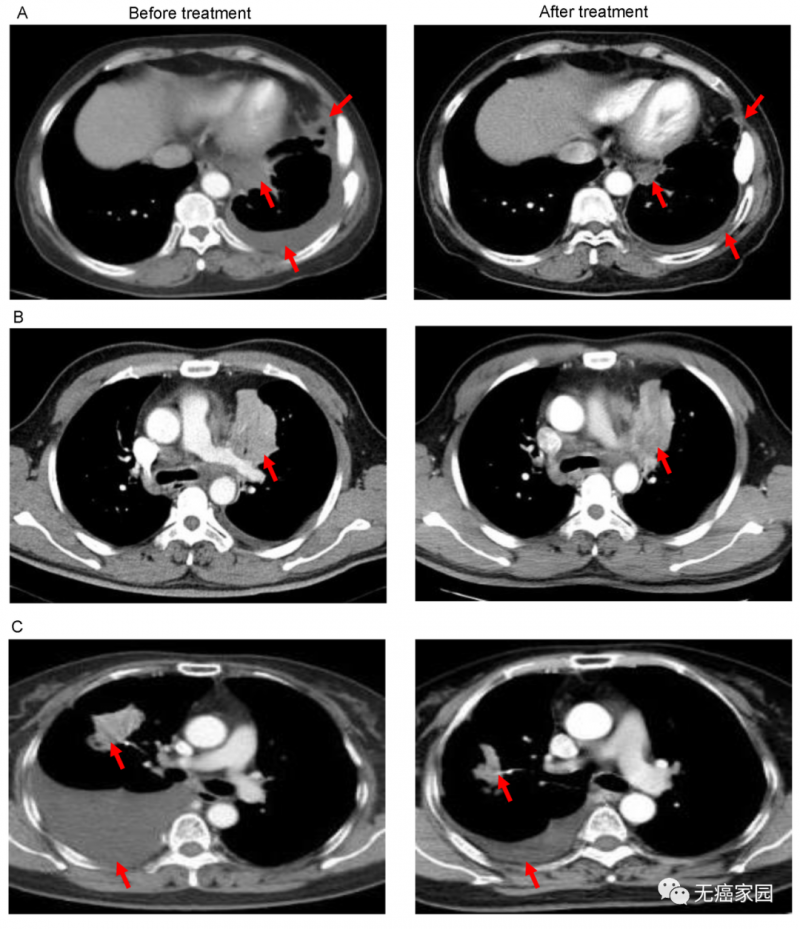

图中显示结束治疗后,患者的肿瘤完全消失

图A中患者1在输注CAR-T细胞后,通过CT扫描显示其胸腔积液减少,转移性肺门淋巴结和胸膜结节轻度缩小(箭头)。

图B中CT图像显示患者8的原发性肿瘤缩小(箭头);图C中CT检查发现CAR-T治疗后患者9的胸腔积液吸收和肺部病变明显消退。